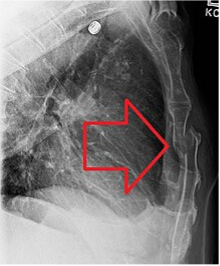

Τα κατάγματα των πλευρών (εικόνα 1) είναι ένας αρκετά συνήθης τραυματισμός, που μπορεί να συμβεί μετά από πτώσεις, πλήξεις, τροχαία ατυχήματα κοκ.

Ο ασταθής θώρακας είναι μία ιδιαίτερη κατάσταση που προκαλείται όταν 3 ή περισσότερες συνεχόμενες πλευρές σπάσουν. Η κατάσταση αυτή είναι ιδιαίτερα σοβαρή, γιατί διαταράσσεται η σταθερότητα του θωρακικού τοιχώματος, η οποία παίζει κεντρικό ρόλο στο μηχανισμό της αναπνοής, με αποτέλεσμα να επιβαρύνεται ο αερισμός των πνευμόνων, δηλαδή η αναπνοή (εικόνα 3). Ο ασταθής θώρακας συστήνεται να αποκαθίσταται χειρουργικά, καθώς η παραμονή του για μεγάλο χρονικό μπορεί να οδηγήσει σε αναπνευστική ανεπάρκεια και επιβάρυνση της πρόγνωσης του καταγματία.

Εικόνα 3. Γραφική αναπαράσταση του τρόπου αναπνοής σε τραυματία με ασταθή θώρακα. Κατά την εισπνοή, το ασταθές τμήμα του θώρακα, αντί να εκπτύσσεται, συμπτύσσεται, συμπιέζοντας τον πνεύμονα και εμποδίζοντας τον αερισμό του. Ασταθής θώρακας μπορεί να προκληθεί επίσης και με άλλους συνδυασμούς καταγμάτων, όπως με συνδυασμό κατάγματος στέρνου και πλευρών ή με κατάγματα συνεχόμενων αντίστοιχων πλευρών εκατέρωθεν του στέρνου. Στην τελευταία περίπτωση το ασταθές τμήμα του θώρακα εντοπίζεται στο πρόσθιο θωρακικό τοίχωμα και περιλαμβάνει το στέρνο.